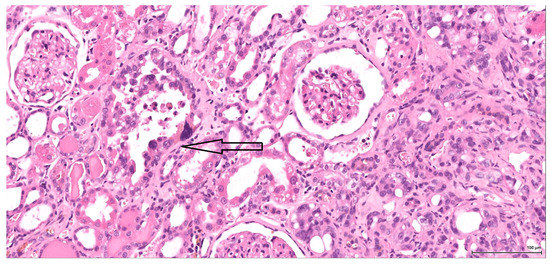

The epithelioid component combines predominantly high-grade cytology with vesicular, nucleolated, mitotically active nuclei and abundant eosinophilic cytoplasm, which only occasionally appears clear. The tumour cells are arranged in a solid pattern, with nested, alveolar and tubular architecture; rarely noted are pseudopapillary structures. Sometimes, cystic or hyaline degeneration is seen. A common finding is necrosis; tumour lobules with central necrosis (comedo-like) are frequently present. The tumour invasion front is mostly of the pushing type (Figure 1).

Figure 1. H&E: Male (case 1): epithelioid morphology, very focal clear cytoplasm, comedo-like tumour necrosis (arrows), pushing-type invasion front.